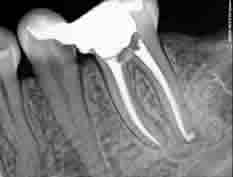

Our practice is equipped with a state-of-the-art root canal treatment system for cleaning and broadening even very narrow root canals and a nickel-titanium (NiTi) rotating instrument system. Sometimes what we usually call a root canal is in fact a whole system of branched or forked canals, spreading like a river delta (hence the name - root delta ). This whole space has to be cleaned and disinfected. Remainders of tissue left over in the canal are a feeding ground for bacteria, which can re-initiate an inflammation.

Thanks to Obtura and Touch'n'Heat thermal condensation technique of root canal filling we can hermetically fill even the most curved and branched canals. A tooth treated that way can successfully serve the patient for many years, and the root itself can be used for future complex prosthetic reconstruction.